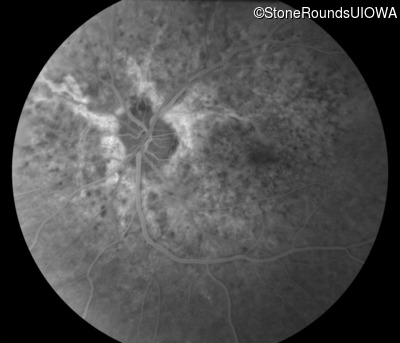

Fluorescein Angiography - Right - 20/20 -1

Exemplar

Fluorescein Angiography - Left - 20/20 -2